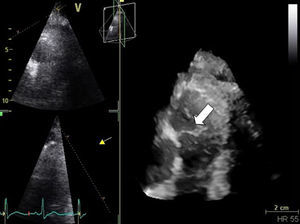

Case reportA 68-year-old man, diabetic with peripheral neuropathy, was admitted to the Internal Medicine ward due to prolonged fever. He reported suffering from both asthenia and fever over the preceding three weeks. He had been given empirical amoxicillin plus clavulanic acid two weeks previously, a treatment that led to transient symptomatic improvement. During initial observation the patient was normotensive with an axillary temperature of 37.6°C. Both cardiac and pulmonary examinations were normal. His right hallux exhibited a lesion, which by his account had been present for the preceding twelve months (Figure 1). Blood tests revealed leukocytosis – 22.70×109/l with 95.8% neutrophils – and elevated CRP (2.14mg/dl). PA chest X-rays were normal. Blood cultures revealed methicillin-susceptible Staphylococcus aureus (MSSA). Transthoracic echocardiography (TTE), and later transesophageal echocardiography (TEE), both revealed a mobile, ovoid, 1-cm diameter mass adhering to the arterial face of the pulmonary valve, and another highly mobile filiform mass also adhering to the PV and protruding into the right ventricle (Figures 2 and 3) without causing any obstruction. Taking into account the antibiotic susceptibility test results, the prescribed antibiotic therapy consisted of flucloxacillin 1000mg IV every 4h and gentamicin 1mg/kg every 8h for six weeks. The fever began to subside on the eighth day. Control echocardiography during hospitalization showed only mild to moderate pulmonary regurgitation. The patient had no other clinical manifestations or identifiable complications, including thromboembolism. Blood cultures were negative after the antibiotic course was completed. The patient was discharged home after six weeks. Nevertheless, the pre-discharge echocardiogram revealed persistence of the vegetations (Figure 4), which had developed a fibrotic appearance, and persistent mild to moderate pulmonary regurgitation.